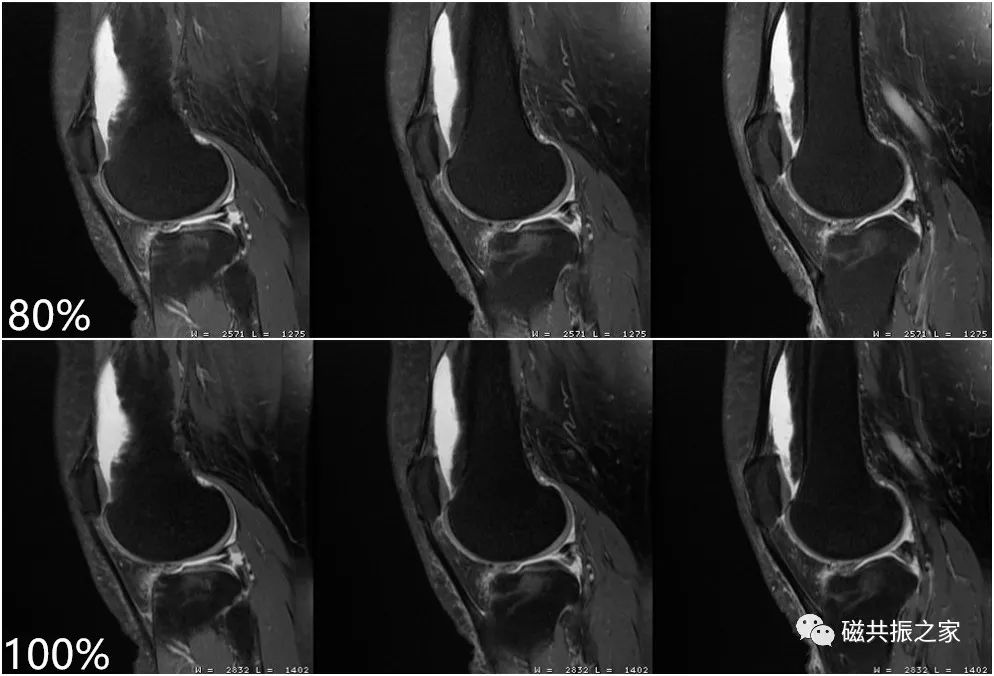

如上图的压脂程度为80%,下图的压脂为100% 。我们知道MRI的信号主要来自于水和脂肪中的氢质子,虽然较强的压脂程度可突出某些组织间的对比,但更多的脂肪被抑制,图像的SNR会下降,则不利于我们做更高分辨率的图像。在小体素扫描时,使用部分压脂可以保证图像足够的信噪比。